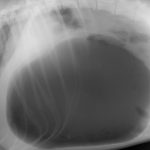

犬に関する診療実績